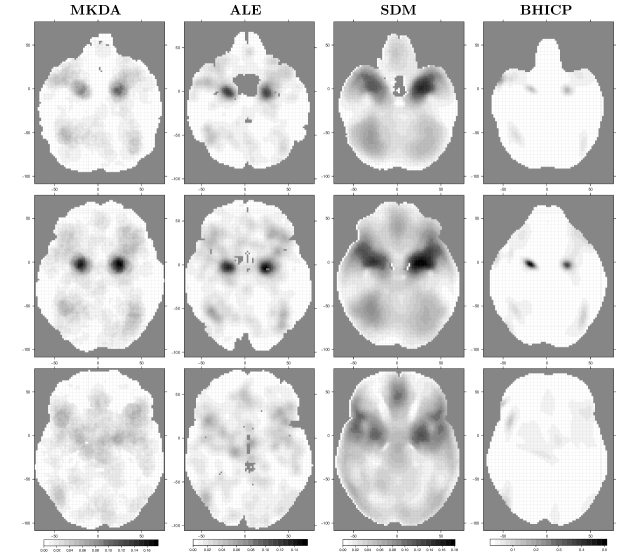

Figure 5 shows statistic images obtained from the four methods presented above, conditional on several values of the z𝑧z dimension. Note that for ALE, MKDA and SDM we show (v)𝑣\ell(v), m(v)𝑚𝑣m(v) and s(v)𝑠𝑣s(v), respectively, whereas for the BHICP we show the voxel-wise posterior mean of the activation study intensity function, namely i=1I[λi0(v)+ρi(v)]superscriptsubscript𝑖1𝐼delimited-[]superscriptsubscript𝜆𝑖0𝑣subscript𝜌𝑖𝑣\sum_{i=1}^{I}{\left[\lambda_{i}^{0}(v)+\rho_{i}(v)\right]}111111Kang et al. (2011) note that singleton foci can also be viewed as activation centers since they come directly from the population centers.. We see that all of the methods provide qualitatively similar results. More specifically, the regions of the brain that are mostly engaged in emotion processing are the right and left amygdala (Fig. 5, top and middle row). This finding is consistent with previous analyses of the same dataset (Kober et al., 2008; Kang et al., 2011; Yue et al., 2012; Kang et al., 2014) as well as results of previous studies (Phelps and LeDoux, 2005; Costafreda et al., 2008). Other regions with moderately high values are the right and left cerebral cortex (Fig. 5, bottom row). For the BHICP, this pattern is only noticeable in the right cerebral cortex.

Figure 5: Qualitative comparison of the CBMA methods in regions of high clustering of foci. Column 1 is the MKDA statistic m(v)𝑚𝑣m(v), column 2 is the ALE statistic (v)𝑣\ell(v), column 3 is the SDM statistic s(v)𝑠𝑣s(v), and column 4 is the study activation center intensity i=1I[λi0(v)+ρi(v)]superscriptsubscript𝑖1𝐼delimited-[]superscriptsubscript𝜆𝑖0𝑣subscript𝜌𝑖𝑣\sum_{i=1}^{I}{\left[\lambda_{i}^{0}(v)+\rho_{i}(v)\right]} for the BHICP. Rows 1-3 correspond to axial slices z=22𝑧22z=-22, z=16𝑧16z=-16 and z=2𝑧2z=-2, respectively. Note that differences in brain shapes across methods are simply due to different masks used by the various algorithms.